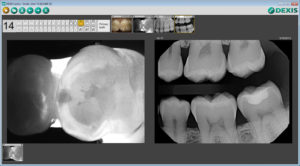

It uses transillumination technology – the image on the screen is similar to that of an X-ray, and the enamel appears transparent while porous lesions appear as dark areas. This is especially helpful for the identification of occlusal, interproximal, and recurrent carious lesions and cracks not visible on other imaging methods.

When a radiolucency on a radiograph is not clear enough for a definitive diagnosis, or if an incipient lesion goes around the interproximal and curves toward the lingual or buccal, a CariVu image offers a big advantage.

Without CariVu, I put a “watch” on that patient’s chart or take an “educated guess” if I see a “darkness” in the interproximal area of the tooth. I would rather have a transilluminated image that shows the carious area with a 99% accuracy* rate than take the chance that the caries may reach the pulp before the patient’s next appointment, or infected structure may be lurking beneath a carious lesion. The CariVu image also shows me if a certain spot can, in fact, just be watched and given a course of preventative care before treatment. During cleaning, the reparative dentin can cause staining sometimes mistaken for caries, and CariVu is an efficient double check for that situation as well.